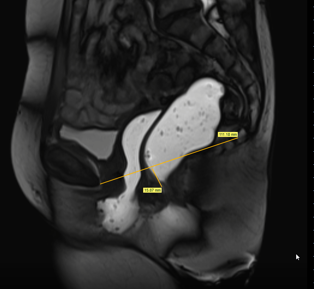

La ligne pubo-coccygienne est la ligne passant par le bord inférieur de la symphyse pubienne et la dernière articulation coccygienne.

- Cystocèle (Figure 2) : descente du fond vésical à plus de 1 cm sous la ligne pubo-coccygienne, sans corrélation systématique avec le caractère symptomatique de cette descente.

- Périnée descendant / descendu : la position du périnée repérée par celle du sommet de l’angle ano-rectal ne doit pas être plus de 40 mm en dessous de la ligne pubo-coccygienne au repos (périnée descendu) ou en poussée (descendant).